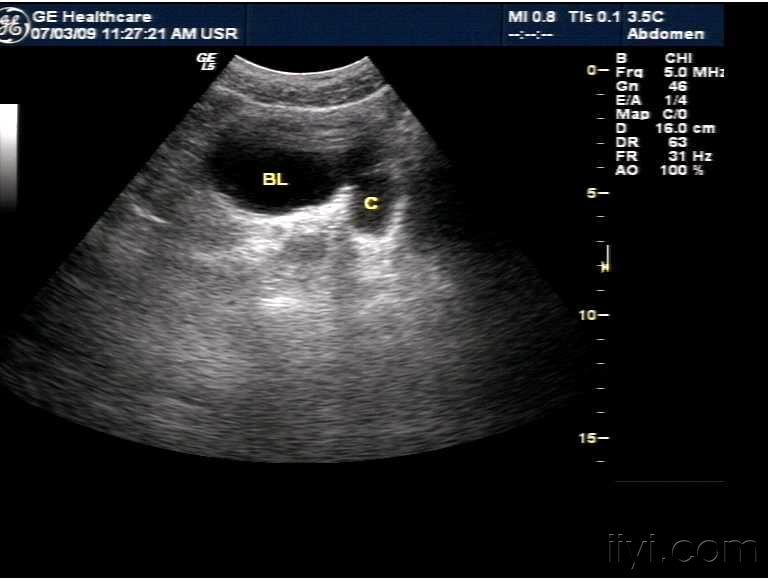

今天看的一例膀胱憩室并结石. - 超声医学讨论版 - 爱爱医医学论坛

图片尺寸768x576